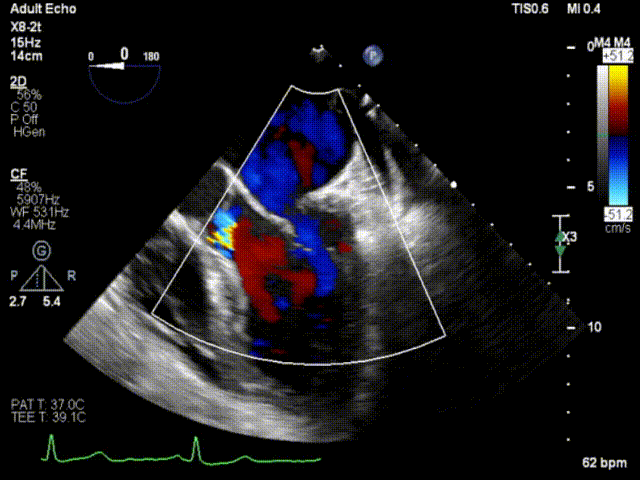

患者男性,63岁,主诉间歇性心悸5年,加重3月。门诊以“二尖瓣关闭不全”收入西京医院。术前超声提示:二尖瓣关闭不全,前叶26mm,后叶22mm,二尖瓣腱索断裂,后叶P1区及部分P2区脱垂,脱垂高度9mm,脱垂宽度15mm,舒张期瓣口面积约6.8cm²,反流束位置位于1区偏2区,Carpentier分型Ⅱ型,心功能Ⅳ级(NYHA分级)。

术前超声心动图1